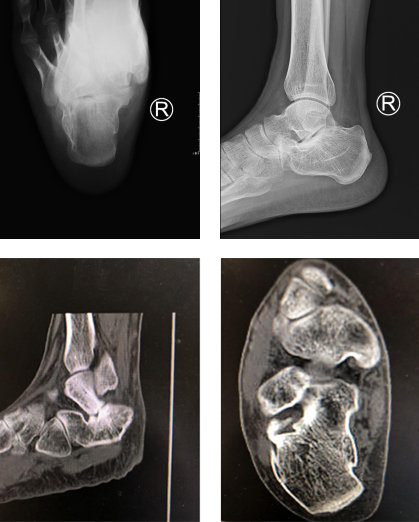

小王多方打听,了解到betway在线登陆有专业的足踝科,于是就来到必威官方首页官网betway,找到了曹广超主任,曹主任了解小王的病情,仔细阅片后,告诉小王,从X片显示,跟骨长度、高度丢失,宽度增加,外侧壁膨出,跟骨后关节面不平整、台阶明显,是典型的陈旧性跟骨骨折、跟骨畸形愈合。

曹广超主任介绍,陈旧性跟骨骨折是指跟骨骨折超过三周,小王从受伤到来我院就诊已经一年多的时间了,骨折端早已畸形生长,所谓畸形愈合是指骨折愈合处的远近骨折断端对线对位不佳,或成角,或旋转,或重叠而成畸形连接,其造成的原因多为整复不良,或固定不确实而使整复后的骨折断端再度移位;或过早地在无保护下的负重而使断端移位,在发生这些情况后又未及时矫正,终于形成畸形愈合。

当天,小王办理了住院手续,然后做了术前的相关检查,明确了诊断之后,曹广超主任赵亮医生团队为小王制定了第二天的手术方案,第二天下午曹主任、赵亮医生团队就在腰麻下为小王做了右跟骨截骨矫形、距下关节融合术,术中沿着跟骨原有的骨折线将跟骨凿开,重新整复,考虑距下关节退变严重,已经没有保留的条件,于是就给予距下关节融合,跟骨截骨矫形内固定治疗,手术后小王平安返回了足踝病房。